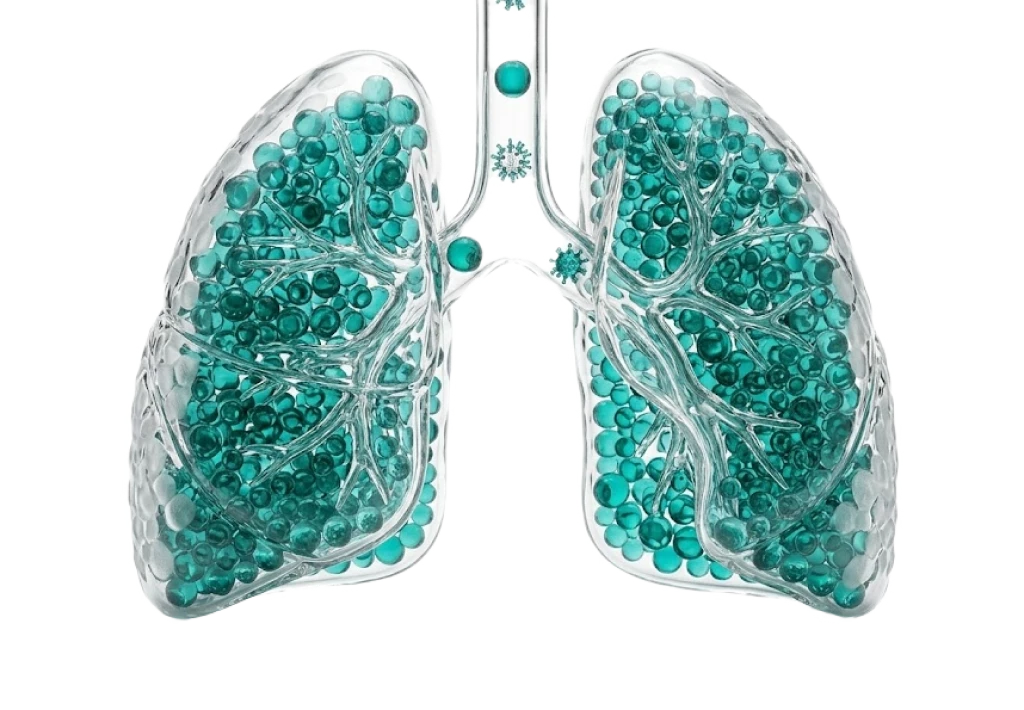

Пульмонология

Инфекционное отделение (паразитология)